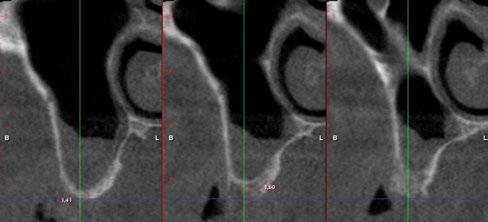

En la exploración radiográfica (OPG, CBCT) observamos la existencia de pérdida ósea interproximal, lesión apical a nivel de la raíz mesial del 27 y el cordal del primer cuadrante incluido y neumatización sinusal del primer y segundo cuadrante.

En el CBCT observamos pérdida ósea posterior superior debida a la neumatización de los senos maxilares izquierdo y derecho. También podemos observar disponibilidad ósea apical suficiente en dientes antero-superiores para la realización de una Implantología inmediata y corticales vestibulares y palatinas conservadas.

Figura 12. Ortopantomografía tras la elevación sinusal. Figura 13. Imagen CBCT tras la elevación sinusal.

3. Fase quirúrgica final

A los 6 meses de cicatrización, se realizó un nuevo CBCT, obteniendo un nuevo archivo DICOM que alineamos con el STL del encerado. De esta manera, se planificó la posición de los implantes a 4 mm del margen de la restauración final y se diseñó y confeccionó la férula de cirugía guiada dentosoportada en 12-13 y 22-23, la cual imprimimos con la impresora 3D Formlabs®. El provisional